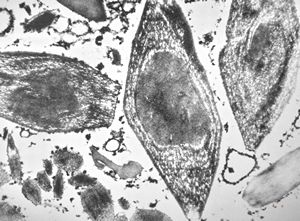

M,26y. | ribosome-lamella bodies in adenocarcinoma

M,41y. | ribosome-lamella complex in tricholeukocyte -hairy cell leukemia, spleen

M,41y. | ribosome-lamella complex in tricholeukocyte -hairy cell leukemia, spleen

M,41y. | ribosome-lamella complex in tricholeukocyte -hairy cell leukemia, spleen